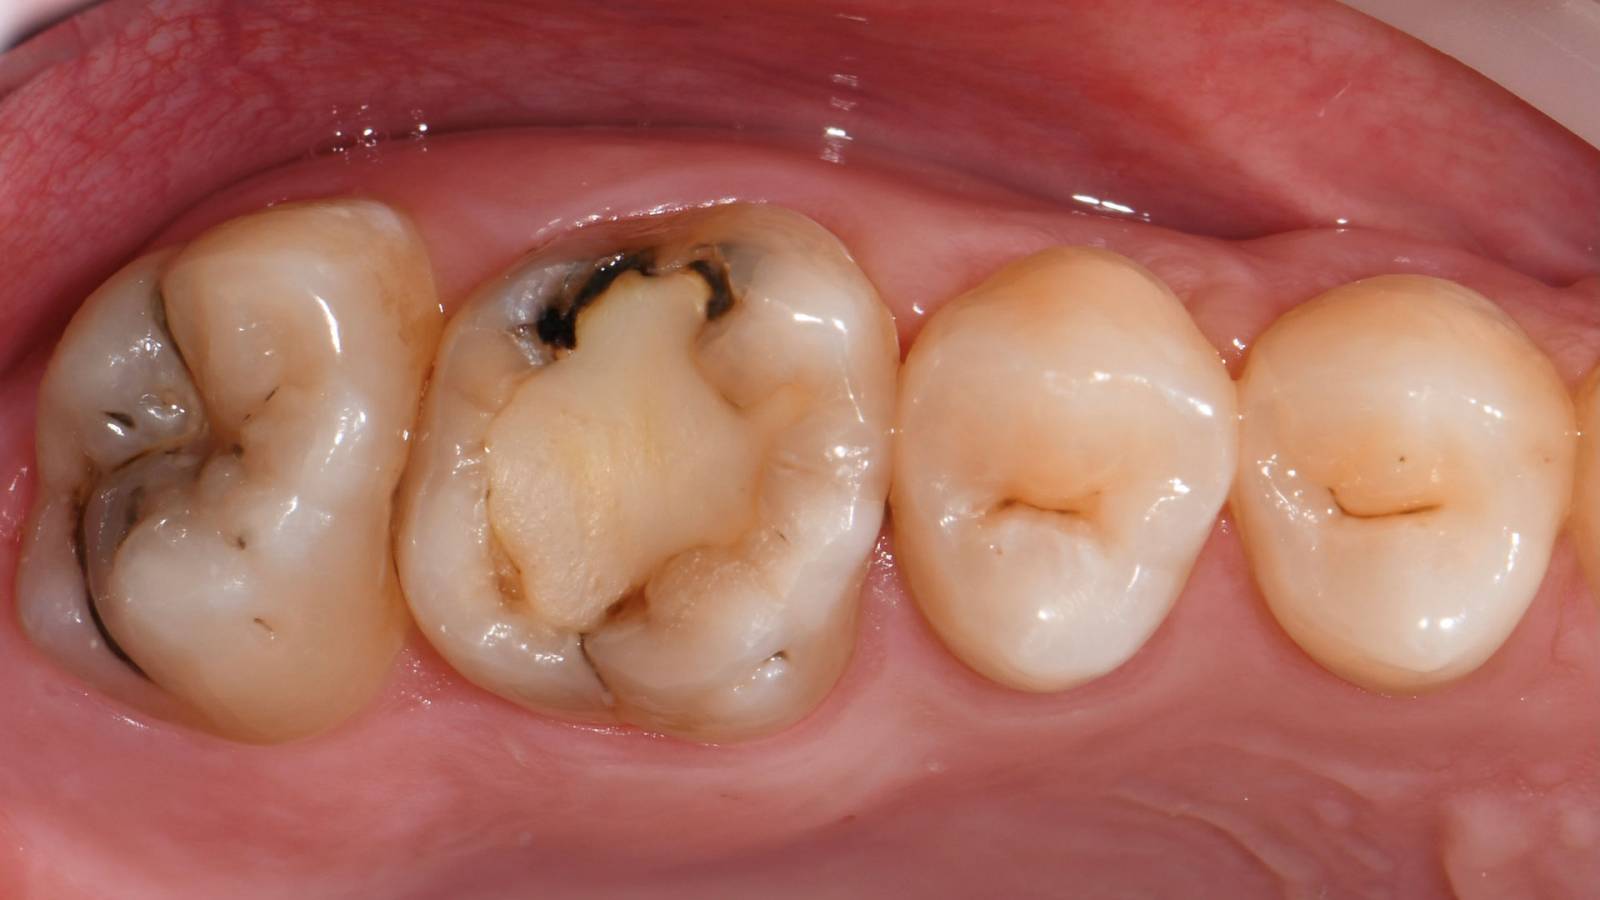

Before

First upper molar had been restored with an extensive yet insufficient composite filling that already showed visible fractures.